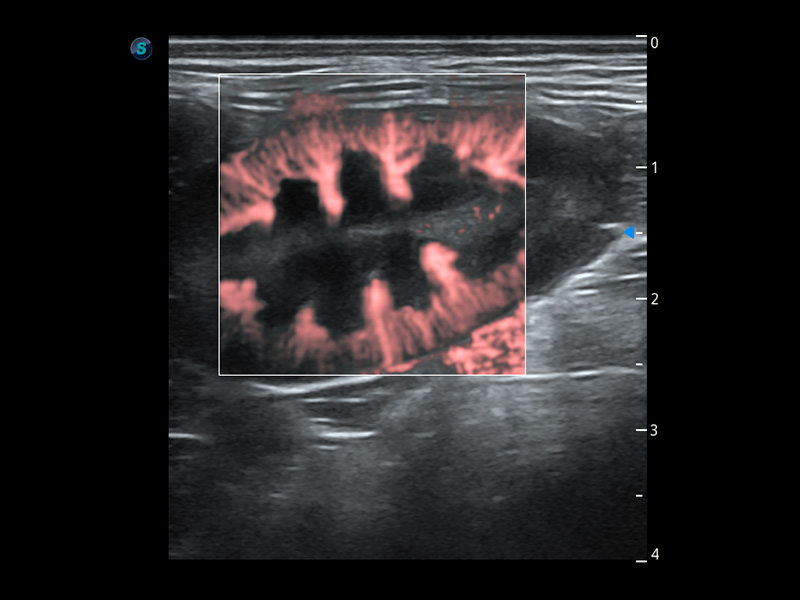

ProPet 60 作為一款高端臺式動物超聲設(shè)備,為動物醫(yī)生的日常診斷提供了一系列貼合動物臨床需求、解決臨床實際問題的高級成像功能。憑借全系列高清探頭,滿足醫(yī)生對腹部、心臟、生殖、淺表、肌骨等成像的所有需求,切實幫助您提升檢查效率,提高診斷信心。

獸用彩色多普勒超聲診斷系統(tǒng)